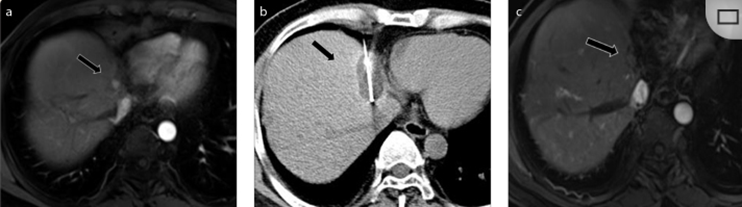

CT引導的冷凍消融

undefined

51歲男性患者,肝移植后復發(fā)病例

(a) 射頻消融后在病變邊緣顯示殘余增強。

(b) 冷凍消融術中影像顯示冰球完全覆蓋病變。

(c) 19個月后隨訪,沒有發(fā)生局部腫瘤進展。